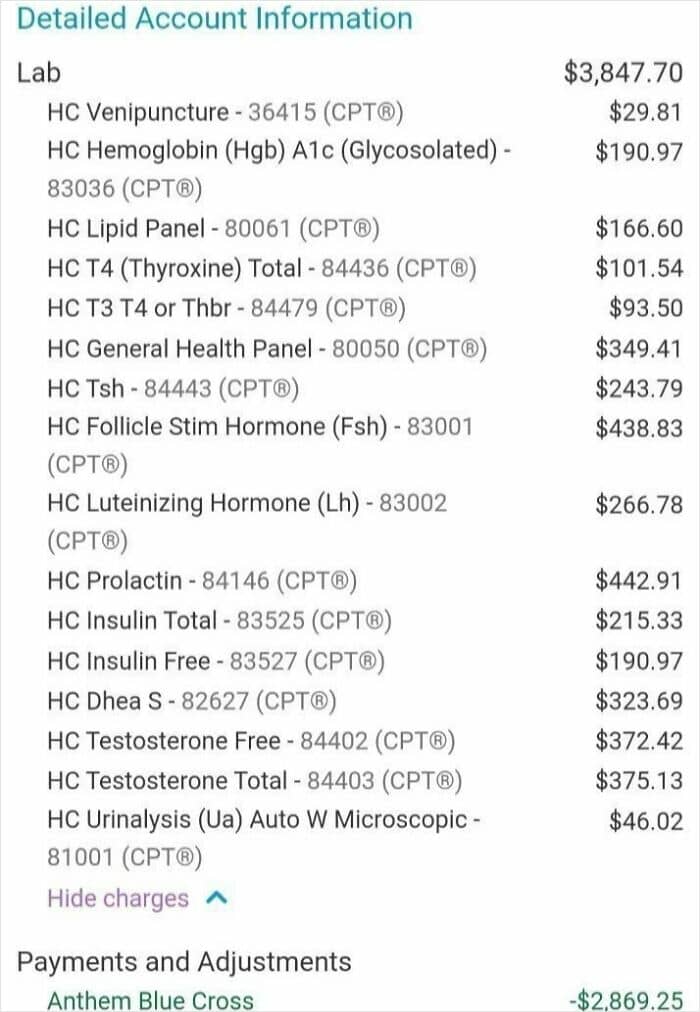

#95 Cost Of My Wife’s Bloodwork At The Hospital I Work For And Get Insurance Through